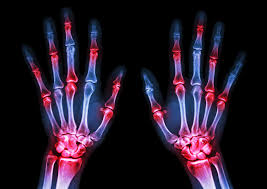

Zastosowanie tofacytynibu w leczeniu chorych na reumatoidalne zapalenie stawów - stanowisko ekspertów PTR

Reumatoidalne zapalenie stawów